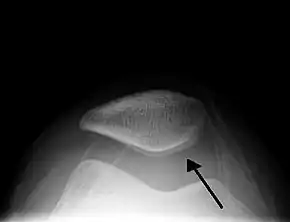

| Traumatic effusion of the right knee, with swelling lateral to the kneecap marked by an arrow | |